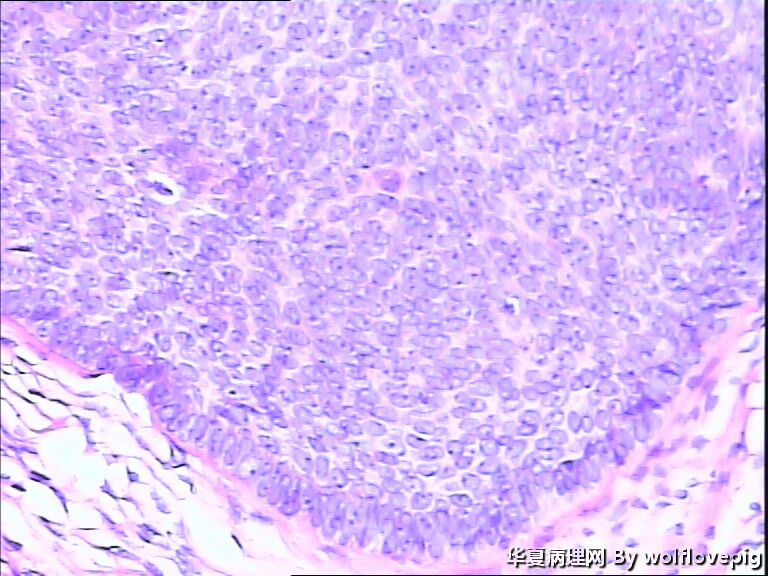

女,58y,右面部包块10年。灰白不整形带皮组织一块:2.3cm*1.5cm*0.3cm,切面有一灰白区域,质软,边界欠清。

图1

诊断考虑毛母细胞瘤,或毛发上皮瘤。

没有基底样物质,没有收缩裂隙,细胞异型不大,无明确核分裂像,考虑:附属器肿瘤,有点像汗腺来源的,如真皮导管瘤或螺旋瘤。请老师指点。

栅栏状外周结构,疏松的间质,基底细胞癌

与表皮无关,表皮无破溃,无收缩间隙-------不支持BCC  有角囊肿 促纤维增生-----支持毛发上皮瘤